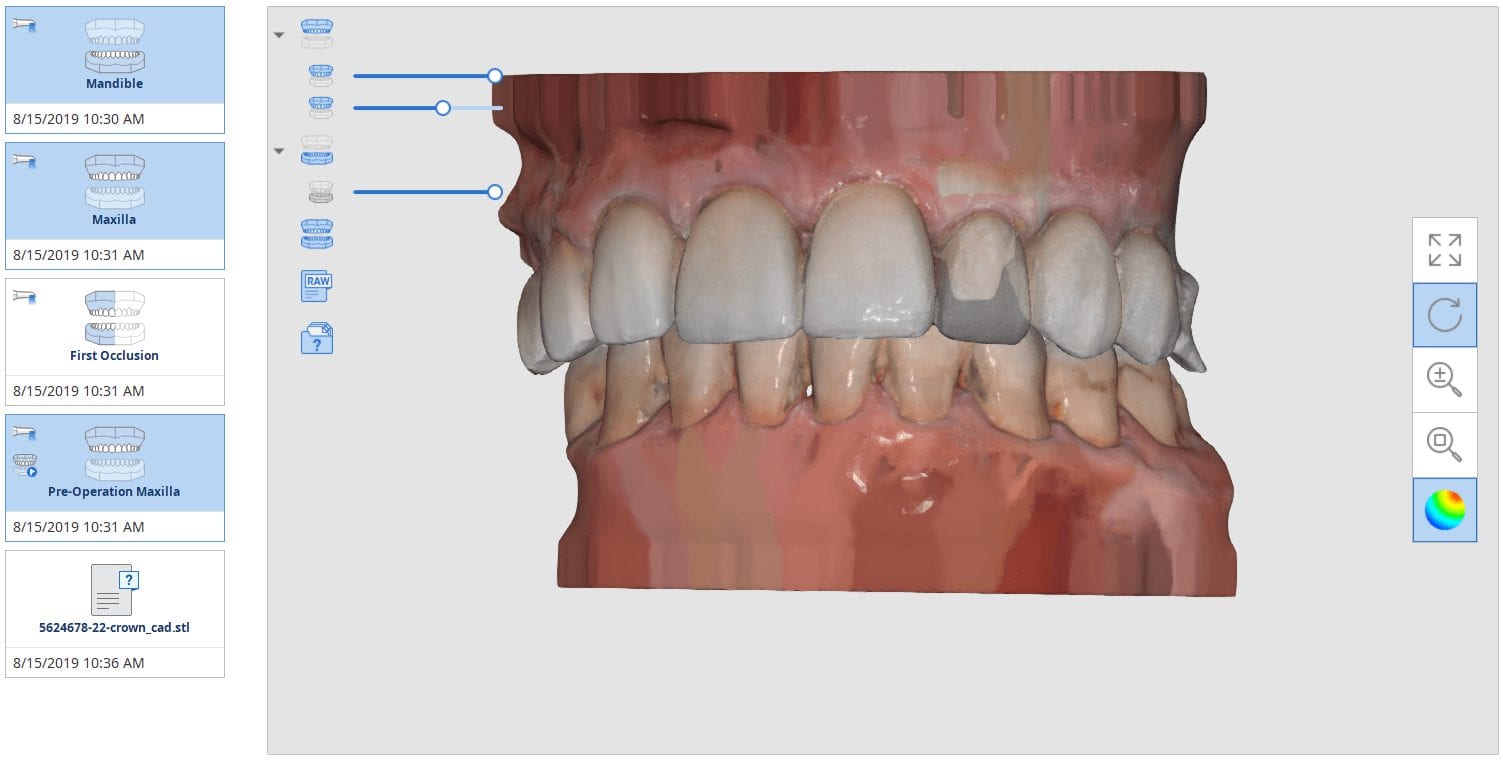

Anterior Copy Crown With Medit i500 Direct Import Into CAD for Design and Mill with CEREC MCXL and CORiTEC ONE

August 15, 2019In this article, we feature an upper left lateral crown that needed to be replaced due to recurrent decay. While the patient was getting numb, we defined the job description […]